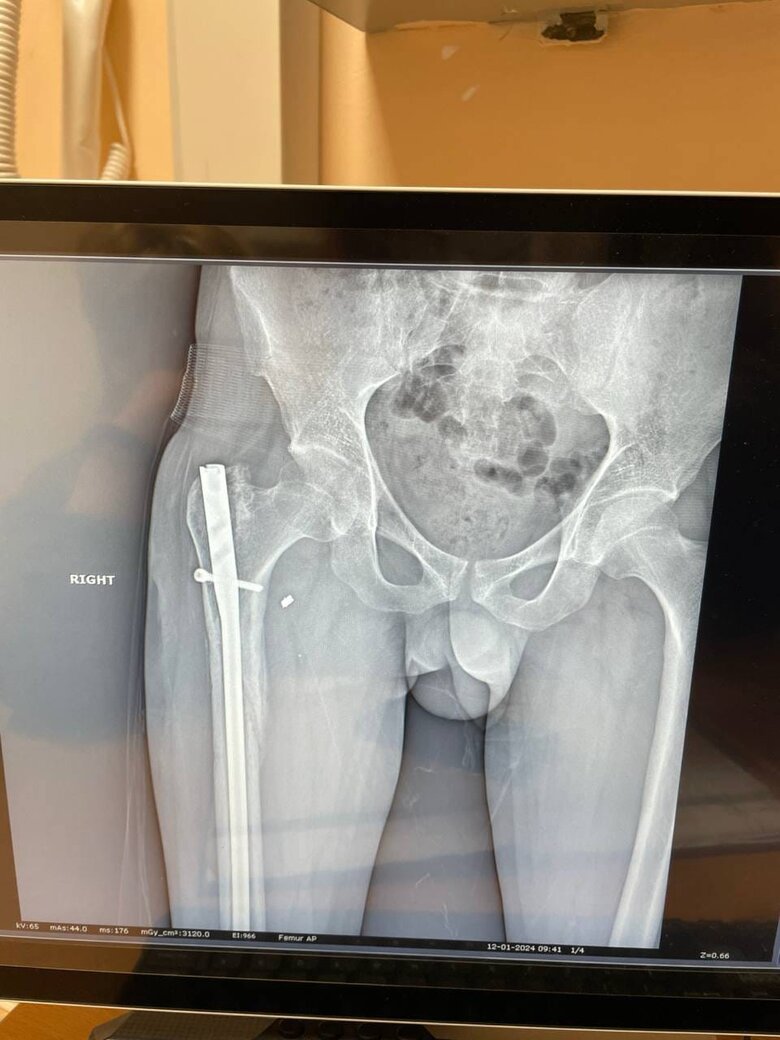

Друзі, знайомтеся: це Алік. Мій боєць, сапер, який отримав важкі поранення влітку минулого року під час штурмової операції південніше Бахмуту. Операція пішла невдало, групу накрили гради. Алік врятував кількох поранених бійців, надавав їм першу допомогу, але й сам зазнав серйозних ушкоджень.

Військовий третьої штурмової бригади Алік

Наразі після тривалого лікування він визнаний непридатними до військової служби і залишився фактично без жодних засобів для існування. Справа не лише в дебільному законодавстві, яке сьогодні залишає таких, як Алік, на узбіччі життя. Алік - сирота, у нього в прямому сенсі нема на кого спертися, окрім побратимів і небайдужих українців, які розуміють, що його жертва була заради нас усіх.